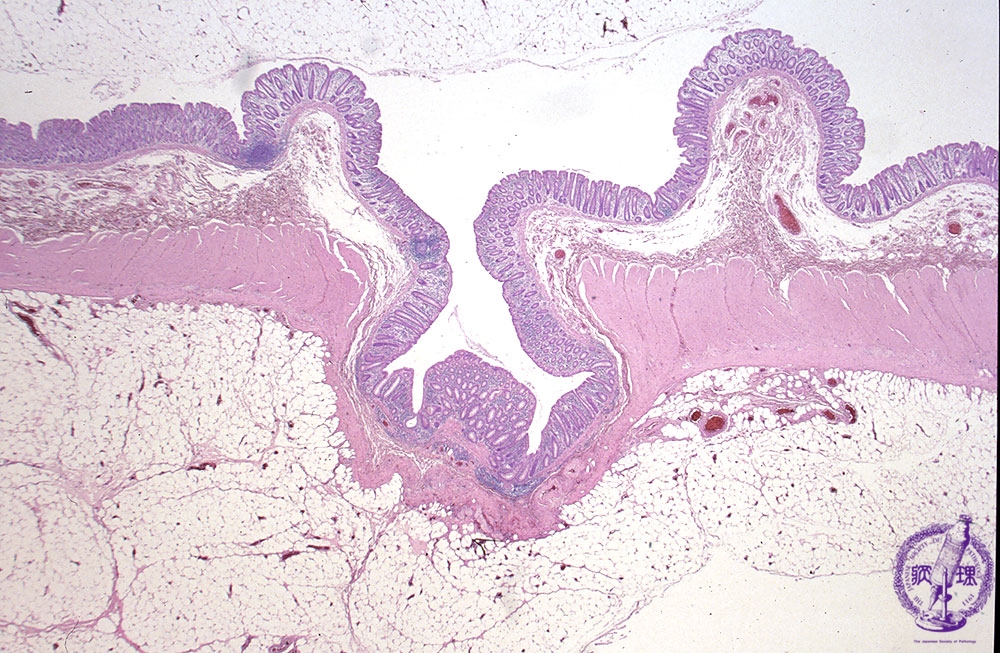

- 9.Small intestine, Large intestine

- (2)Diverticulosis of large intestine (diverticulitis) >

Microscopic view (H&E stain, low power): Both mucosa and the underlying muscularis propria protrude through the external bowel wall.

Click the image to see the enlarged image.